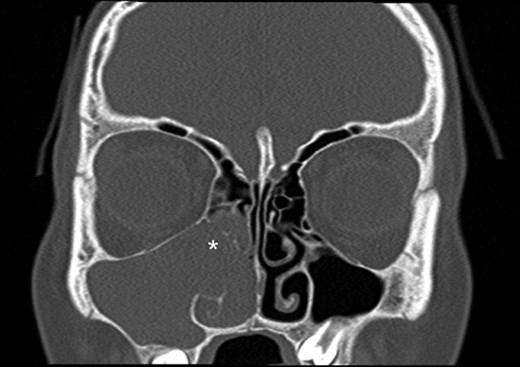

Computerized tomography (CT) and magnetic resonance imaging (MRI) confirmed the presence of a large right-sided sinonasal mass extending posteriorly to the nasopharynx. Irregularity was noted along the posterolateral wall of the maxillary sinus (Figs 1 and 2). In view of the age, sex and clinical presentation, a provisional diagnosis of juvenile nasopharyngeal angiofibroma (JNA) was made.

Coronal computed tomography (bone window) image showing a right-sided antrochoanal mass (white asterisk) extending in to the maxillary and ethmoidal sinuses.